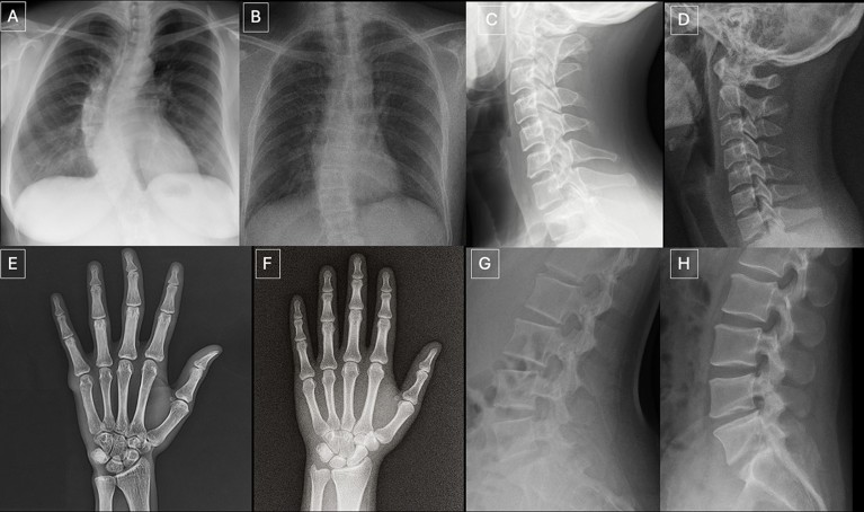

左侧为人体不同部位的真实X光影像,右侧为AI生成的X光影像。你能看出差别吗?来源:Radiological Society of North America (RSNA)

放射科医生与大语言模型均难以区分真实的X光影像与AI生成的X光影像。在一项研究中,研究人员让17名放射科医生评估一系列X光影像的技术质量,仅有41%的医生担忧数据中混入了AI生成的影像。在识别伪造影像的测试中,ChatGPT等大模型的准确率仅为57% - 85%。该研究共同作者、放射科医生Mickael Tordjman.表示,这些AI生成的影像可能会污染科学文献,也可能影响保险理赔。此类影像还可能混入用于解读医学影像的AI模型的训练数据,导致模型输出结果出现偏差。(参考文献:Radiology 论文)